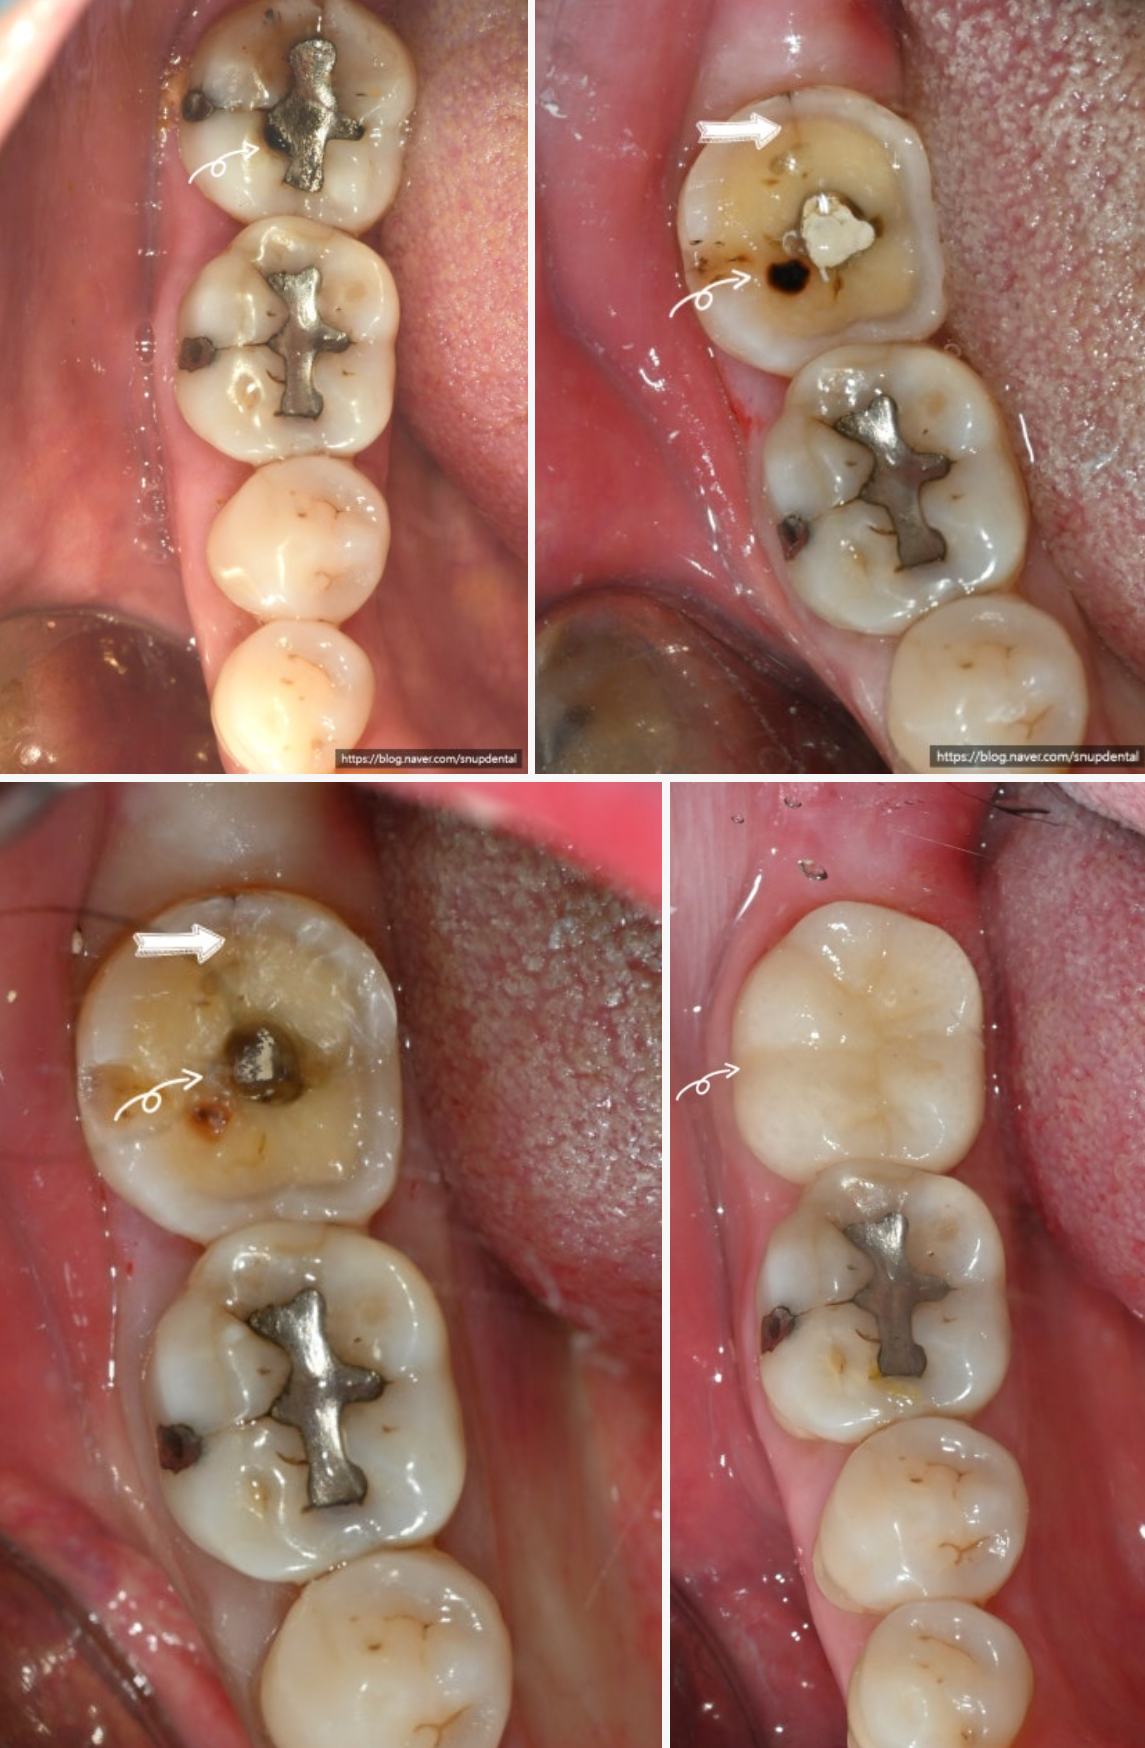

오른쪽 아래 두 번째 어금니 불편감(통증) 호소

아말감 부분 파절 및 이차우식 소견

치아 crack 소견(굵은 화살표)

임시치아 상태에서 불편감이 없어 근관치료 없이 크라운(지르코니아) 치료로 마무리.

앞의 어금니도 치료 원하셨으나 치료가 필요한 상태는 아니라 더 사용하시기로 함.